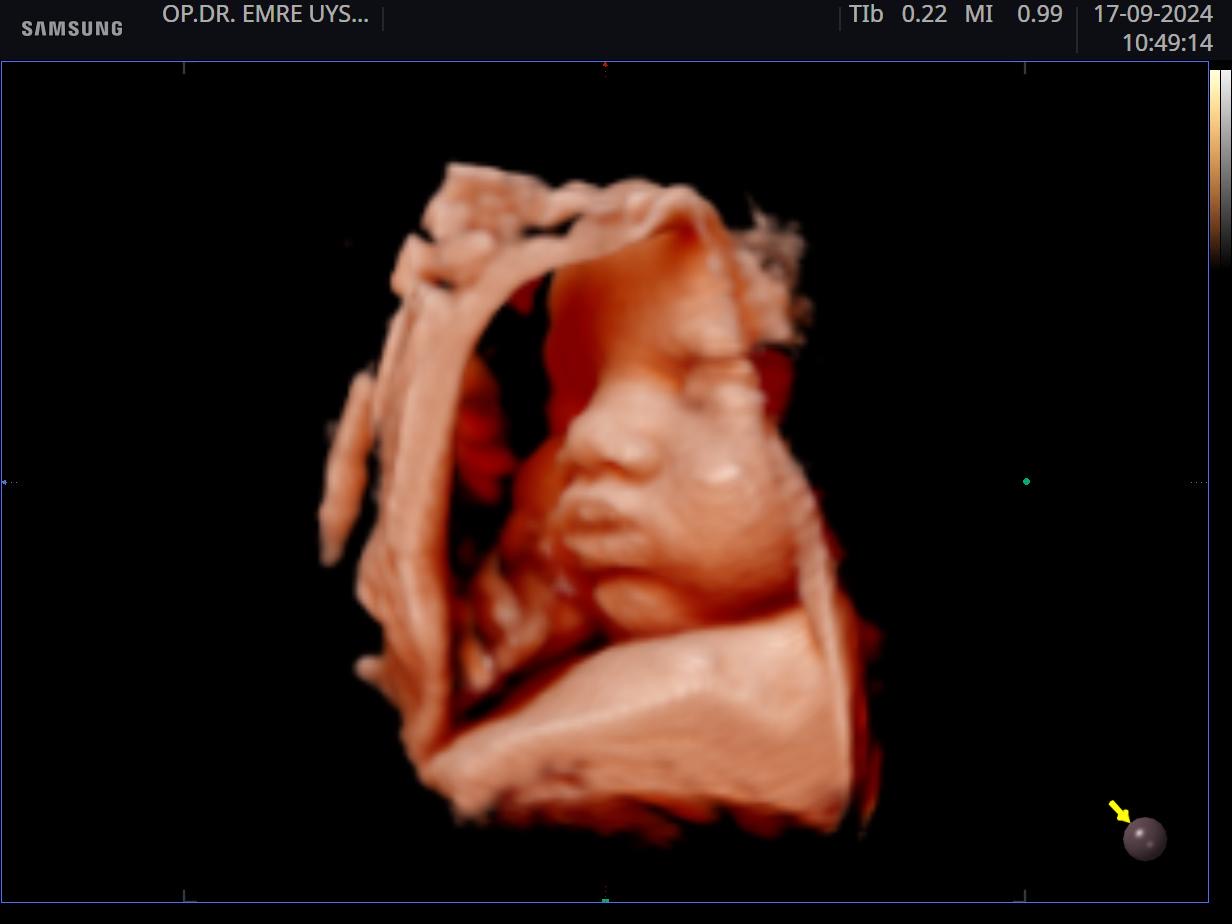

Her kadının hayatında önemli dönüm noktaları vardır. Hiç şüphesizki hamilelik süreci ve doğum bunlardan en kıymetlisidir. Biz de bu değerin farkındayız ve 15 yılı aşan tecrübemiz ile minik mucizenize sağlıkla kavuşma yolculuğunda sizin yanınızdayız. 4d ultrason ile bebeğinizin sağlığını yakından takip ederken, klinik takibimiz ile de süreci eğlenceli ve sağlıklı bir şekilde geçirmeniz için elimizden gelenin en iyisini yapıyor olacağız. Yaşasın Hamilesiniz!